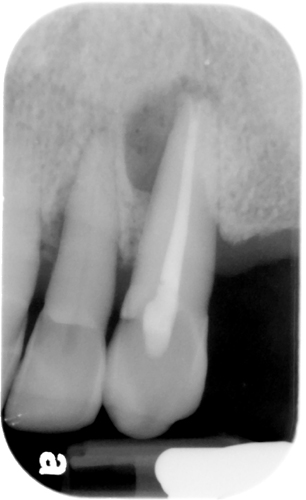

Clinically: painful, diffuse, reddened swelling affecting the right side of the face, centred on the cheek, causing partial closure of the eye. This developed overnight. The previous 3 days there had been, according to the patient, ‘an abscess’ present on UR3. The patient feels unwell and there is lymphadenopathy present. UR3 is grossly carious. Radiologically: UR3 has a periapical rarefying osteitis.

Oh, and if you peek inside their mouth, UR3 is a total disaster zone – super decayed. And to make things even more interesting, when you take a look at it on an X-ray, there’s this periapical rarefying osteitis party happening.